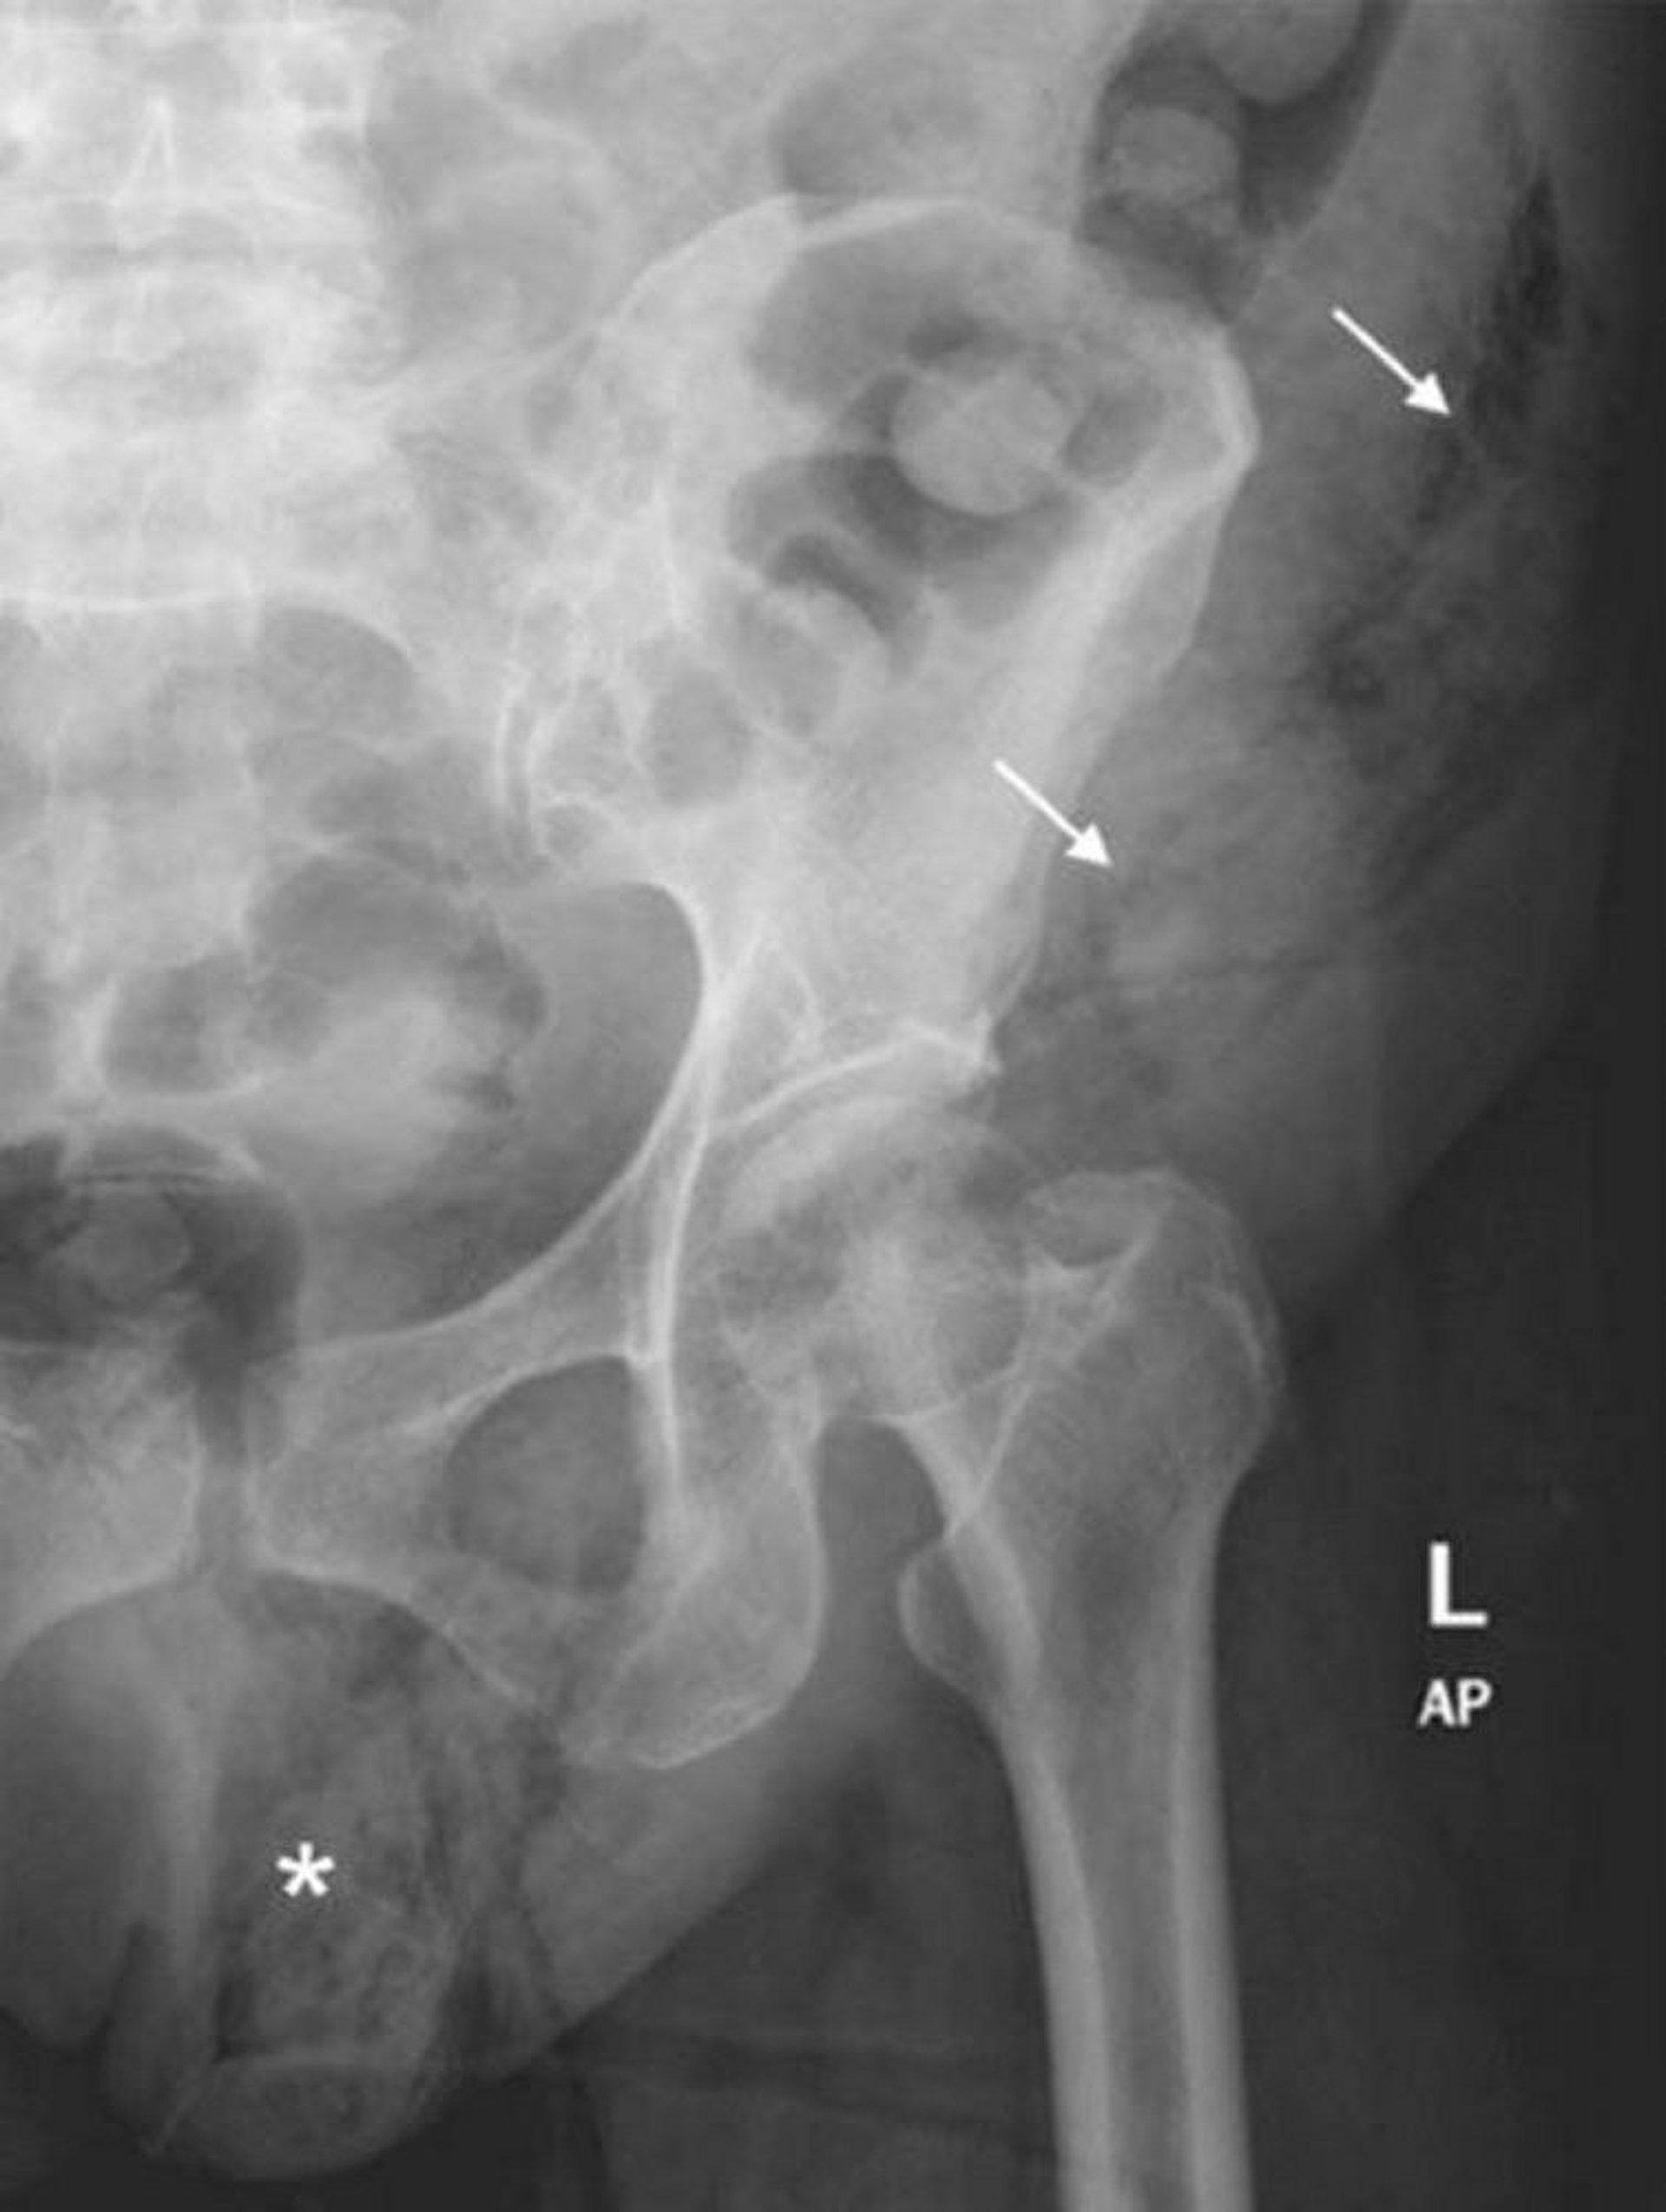

Fournier-Gangrän (Röntgenaufnahme des Abdomens)

Diese Röntgenaufnahme des Abdomens zeigt eine Ausdehnung des Weichteilgases vom linken Hemiskrotum (*) auf die linke Bauchdecke (Pfeile).